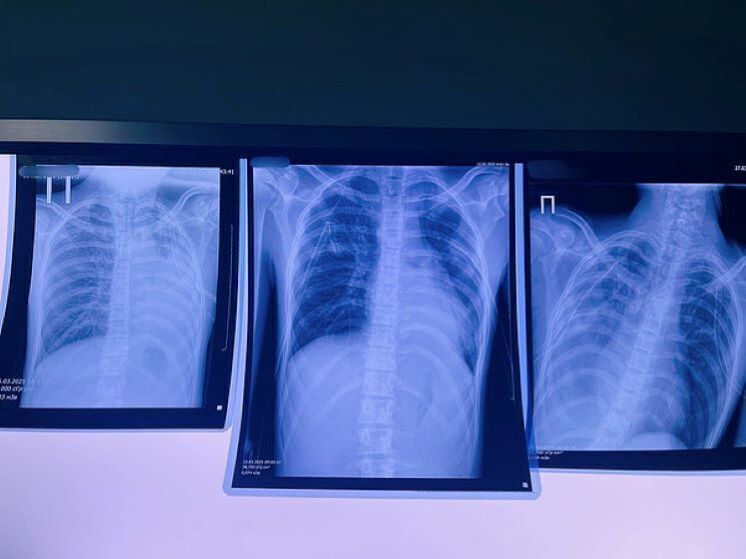

Курение

Вред, однозначно. Хотя для тех, кто не может избавиться от пагубной привычки, некурение - тьма. Остается надеяться, что в борьбе с курением, которая давно приносит свои плоды на Западе и набирает обороты в России, адепты здорового образа жизни рано или поздно одержат полную и окончательную победу.